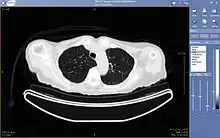

The architecture is the physical implementation of required functionality, or what one sees from the outside. There are different views, depending on the user. A radiologist typically sees a viewing station, a technologist a QA workstation, while a PACS administrator might spend most of their time in the climate-controlled computer room. The composite view is rather different for the various vendors.[2]

Typically a PACS consists of a multitude of devices. The first step in typical PACS systems is the modality. Modalities are typically computed tomography (CT), ultrasound, nuclear medicine, positron emission tomography (PET), and magnetic resonance imaging (MRI). Depending on the facility's workflow most modalities send to a quality assurance (QA) workstation or sometimes called a PACS gateway. The QA workstation is a checkpoint to make sure patient demographics are correct as well as other important attributes of a study. If the study information is correct the images are passed to the archive for storage. The central storage device (archive) stores images and in some cases reports, measurements and other information that resides with the images. The next step in the PACS workflow is the reading workstations. The reading workstation is where the radiologist reviews the patient's study and formulates their diagnosis. Normally tied to the reading workstation is a reporting package that assists the radiologist with dictating the final report. Reporting software is optional and there are various ways in which doctors prefer to dictate their report. Ancillary to the workflow mentioned, there is normally CD/DVD authoring software used to burn patient studies for distribution to patients or referring physicians. The diagram above shows a typical workflow in most imaging centers and hospitals. Note that this section does not cover integration to a Radiology Information System, Hospital Information System and other such front-end system that relates to the PACS workflow.